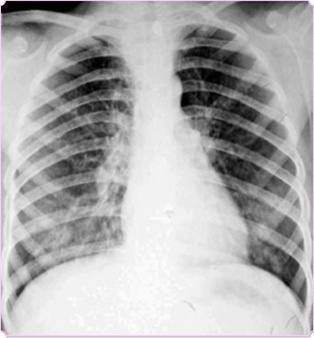

满肺可见“满天星”,根据公式诊断肺转移瘤